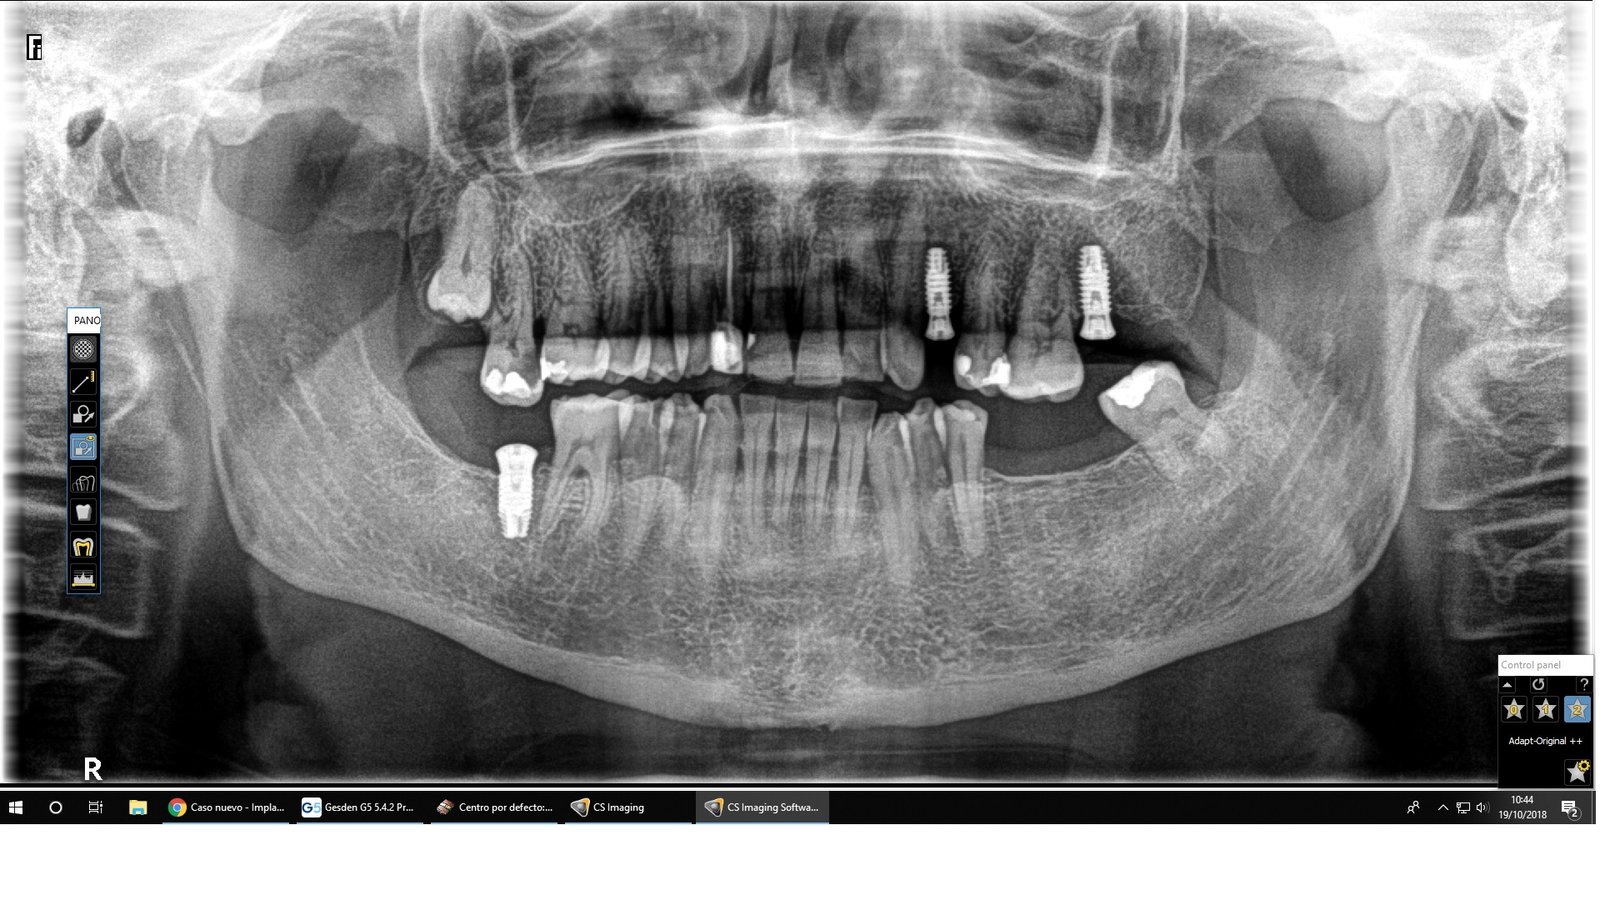

Buenas, compañeros. Pretendo rehabilitar a esta paciente “nómada de clínicas”. Cómo podréis ver tiene al menos 3 tipos de implantes, todos colocados en España desde hace unos 10 años los [...]

Me gustaría saber la marca de los implantes que se ven en la ortopantomografía adjunta, colocados hace unos 10 años en la clínica del doctor Ignacio Corral Pazos. Llevan tapones [...]

Necesito identificar los implantes que lleva puestos este paciente para planificar el caso. Creo que son todos iguales. La radiografía es de hace unos años pero el paciente ha reaparecido [...]